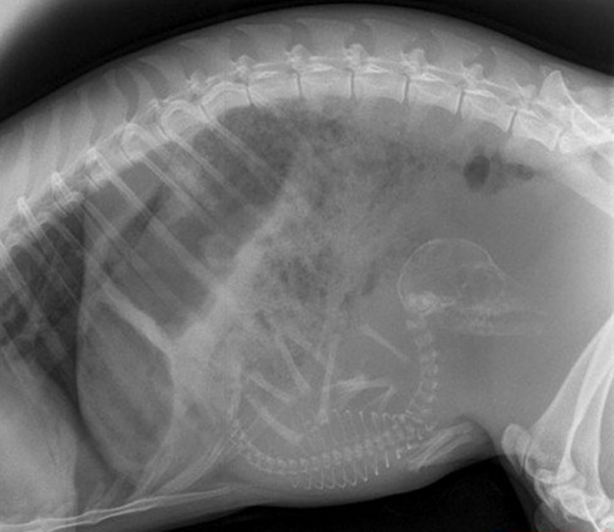

Hamile bir kedi ve onun röntgen filmi.

Hamile kedi

#16

Foto - Röntgen sonrası çıkanlar doktorları bile şok etti! İşte açıklanamayan o görüntüler

Hamile bir kedi daha